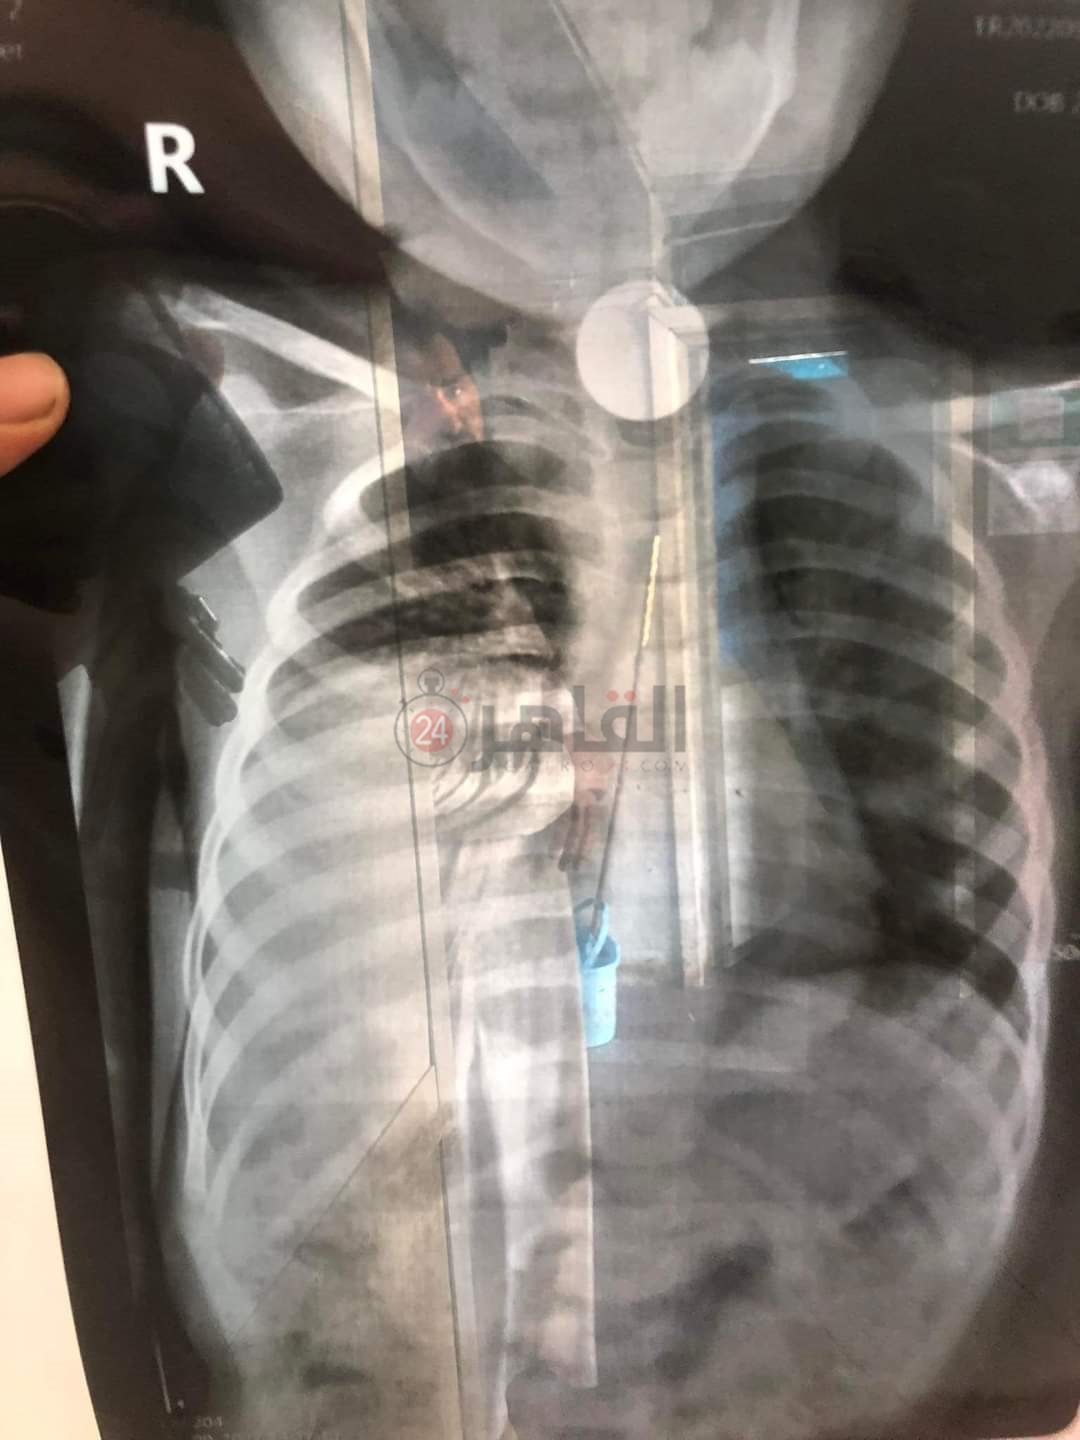

وأكد الدكتور أحمد الشرقاوي، أخصائي الأنف والأذن والحنجرة بالمستشفى التعليمي بالمنوفية، لـ القاهرة 24، أنه تلقى استغاثة من أسرة طفل بعد أن ابتلع جنيها معدنيا عن طريق الخطأ، ووقف خلف الحنجرة، وعلى الفور تم احتجازه والتحضير للتعامل مع الحالة، مشيرا إلى أن العملة المعدنية سدت مجرى الطعام بشكل كامل ومجرى التنفس بشكل جزئي.